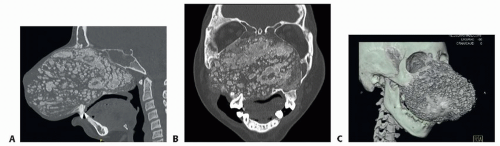

FIG 2 • Lateral (A) and anterior (B) views of a patient with large lower zone 1 fibrous dysplasia. Important nasal airway involvement is seen.

High-resolution CT (1-mm cuts) is the preferred imaging modality, providing useful information for diagnosis, follow-up, and surgical planning. Three-dimensional (3D) reconstruction can further assist in surgical planning.

Provide more accurate information regarding lesion size, location, surrounding structures, and potential compression sites (FIG 3).

FIG 3 • CT scan of patient with large lower zone 1 fibrous dysplasia. A. Sagittal cut. B. Coronal cut. C. 3D reconstruction.

Bones affected by FD are usually expanded with intact cortices. Normal corticomedullary differentiation is lost. The margin between abnormal and normal bone is often difficult to identify because the two regions blend into each other.